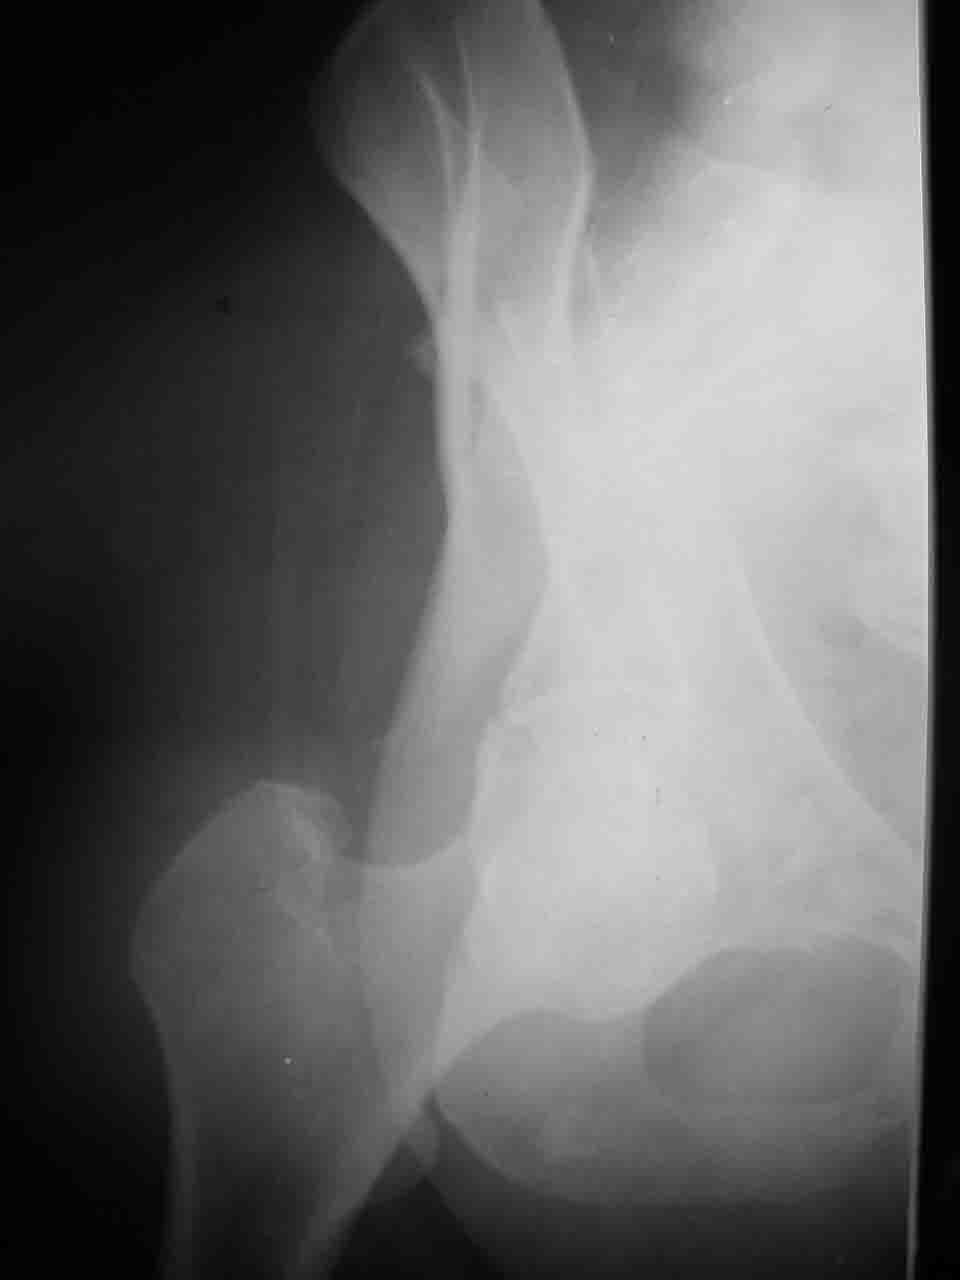

Логика подсказывает, что все-таки лучше иметь анатомически полноценную впадину, хотя ранее упоминалось состояние вторичной конгруэнтности и одно наблюдение у меня есть, когда у больного с полностью нарушенной анатомией впадины и подвывихом головки бедра кзади и кверху боли отсутствовали при относительно достаточном для стиля жизни больного объёме движений. Но это только одно наблюдение и кроме перелома впадины у этогобольного была и тяжелая ЧМТ в анамнезе. Основываясь на формулировке структуры ацетабулюм Э. Летурнеля - как перевернутой буквы Y, впадина для полноценной функции сустава должна иметь сферичность, соответствующую размеру головки бедра и если один из компонентов в дефиците, то функциональные последствия рано или поздно проявятся.

> передним доступом на двухколонный перелом?

Илеофеморальный доступ не совсем передний и сравнительно с илеоингвинальным, и Кохера-Лангенбека открывает весь наружный таз кроме самых передних отделов лонных костей, фиксацию которых я не ставил в задачу. Обширность диссекции, большая длительность операции и более высокий риск гетерооссификации - отрицательные моменты в обмен на возможность легче ориентироваться.

Вопрос доступа к вертлужной впадине при остеосинтезе задача не простая. Конечно, у Летурнеля и Тайла всё давно описано, нам остается только брать на вооружение. Но сами понимаете, что не бывает двух одинаковых ситуаций, поэтому в каждом случае вопрос решается сугубо индивидуально. Наша главная цель - восстановить анатомию с нанесением минимальной дополнительной травмы тазобедреннному суставу, думаю с этим никто не поспорит. Расширенный илиофеморальный доступ уж слишком травматичен (как сказал один коллега "таз лежит отдельно, больной отдельно").Стоит ли делать из пациента анатомический препарат для того чтобы легче ориентироваться. Да и нужно ли собирать всю "мозаику"? Мы применяли при таких операциях своеобразную операционную хитрость - сначала устраняли грубое смещение крыла под гребнем с фиксацией так называемой "плавающей" пластиной (временно фиксированной на двух винтах)- доступ или продлевали боковой, или делали небольшой дополнительный разрез над гребнем. Это позволяло устранить грубое смещение и захождение отломков тела повздошной кости, что значительно облегчало репозицию и остеосинтез впадины над сводом. Основное внимание конечно же уделяли нагружаемому задне-верхнему отделу. Сообщите ваш адрес, пришлю схемы и рентгенограммы.